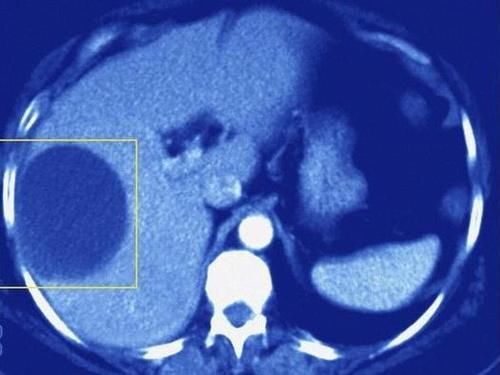

囊肿

囊肿也可发生在多个器官,其中肝囊肿和肾囊肿较为常见。囊肿是一种非常常见的良性病变,实际上类似于水泡。它的主要成分是水。正常情况下,囊肿不会对我们的身体产生任何影响,也不会影响器官的功能,所以一般不需要特殊治疗。

文章插图

【 结节|结节、息肉、囊肿、增生,哪个是癌症“先兆”?一文给你说清】至于一些体积较大的囊肿,如大于5cm,还有压迫症状,如进食后饱胀、恶心、呕吐、疼痛不适等。建议此时进行适当的治疗和处理。治疗方法比较简单,常用的方法有b超引导下囊肿穿刺抽吸术、囊肿“开窗术”等。